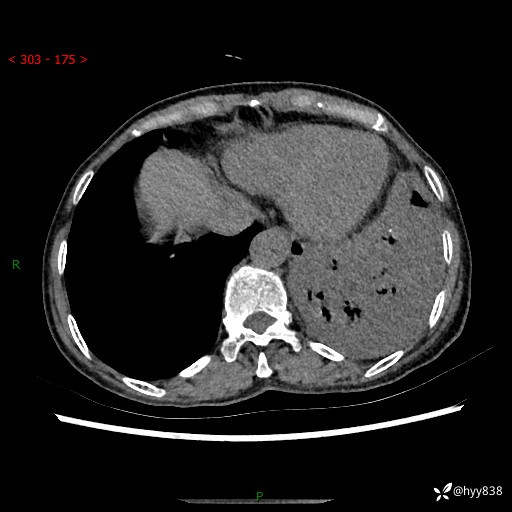

胸部CT平扫+增强